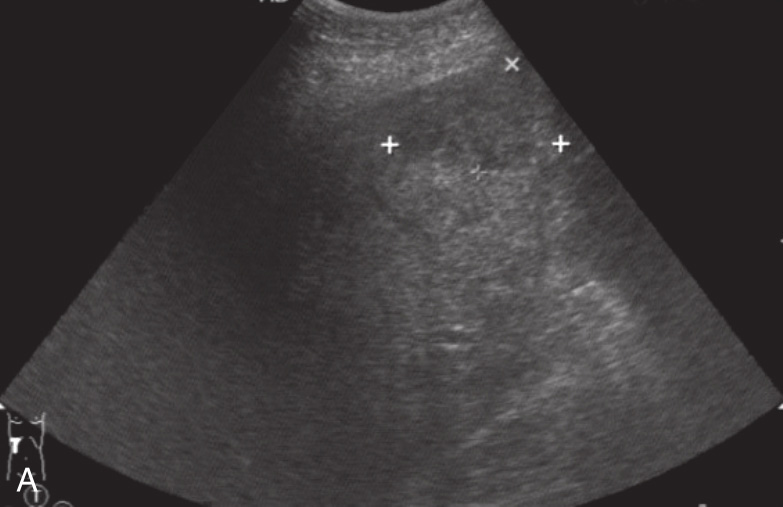

图1-12-1 真性肝破裂灰阶超声图像

A.肝右叶近被膜处片状低回声区;B.肝下积液